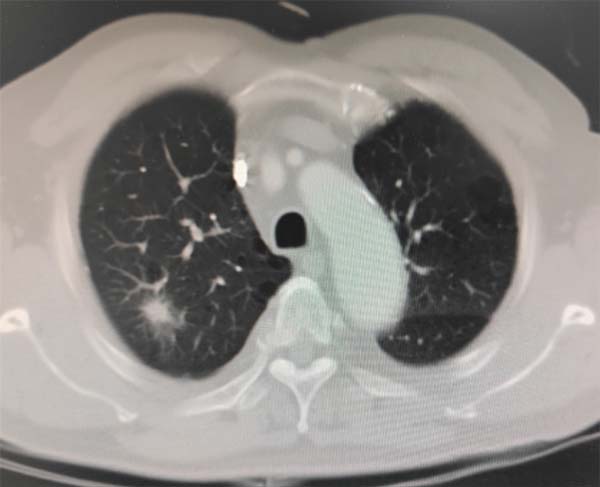

患者CT影像

72岁的老人来自京外,体检做胸部CT时发现肺部多发小结节,其中右肺上叶的一个1.5厘米的结节被判定性质可疑,医生建议行病理检查明确病变性质。这个位置的病理检查一般采取经皮肺穿刺活检,但是老人合并有其他疾病,穿刺出血风险较大,更重要的是老人局麻下体位配合有一定困难,那么能否通过电子支气管镜检查来取得病变组织标本呢?患者及家属辗转多家医院,专家给出的意见是:这个部位支气管镜检查难度大,对技术操作和临床经验要求非常高,建议到应急总医院就诊。

张楠教授团队对老人进行了细致检查和病情讨论,明确右肺病变有组织活检的必要,患者虽然年龄较大并有合并症,全麻下行无痛支气管镜检查难度大,但是本院麻醉科对于支气管镜下共享气道的麻醉经验丰富,如果有硬质气管镜及高频通气呼吸机等支持,术中两科密切协作,安全麻醉及完成检查是有把握的。另一难点是病变位置已达肺叶边缘,支气管分级已达5级支气管以下,从CT影像分析,病变内无明显支气管通气征,提示没有支气管直接通入病变内,即使应用超薄支气管镜及活检鞘管可以到达病变附近,但最后一程也会失去镜下视野,如何确保活检探头准确到达病灶内部是关键问题,如果通过内镜中心配置的电磁导航系统,可以完成无视野导航。